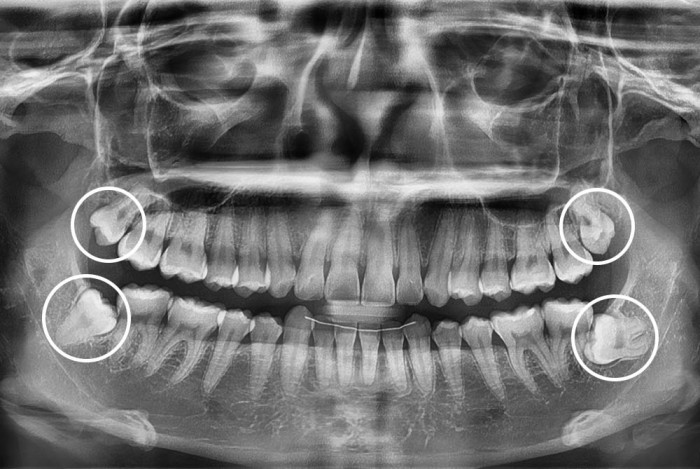

[사랑니] 사랑니

치료후 : 2025-10-31

세종치과는 구강악안면외과학 박사이신 원장님이 발치하는 치과입니다.